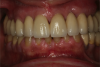

Fig 12. Frontal view (Fig 12) and occlusal view (Fig 13) of clinical application of dual-axis principles. (Images courtesy of Costa Nicolopoulos, BDS)

Figure 12